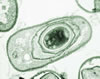

Hastane mikrobu veya hastane enfeksiyonları.Hastane kökenli infeksiyonlar. Hastanın hastaneye yatışından en az 48 saat sonra gelişen enfeksiyonlardır.